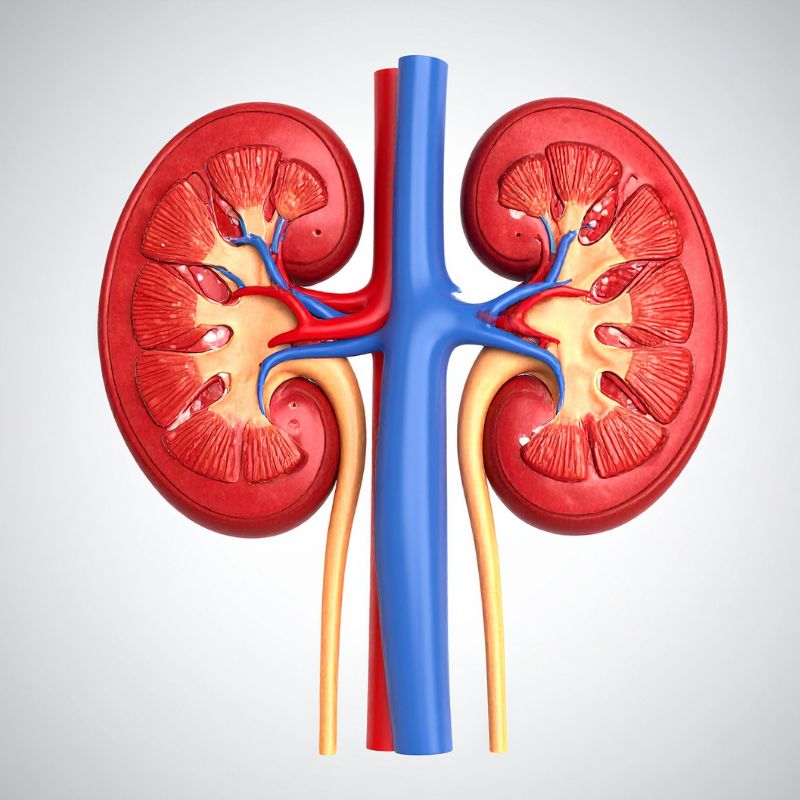

5. Kidney Stress or Elevated Creatinine Levels

Creatinine levels can appear high on blood tests, not because creatine is damaging the kidneys, but because your body is breaking down creatine normally.

Research confirm that standard doses are safe for healthy adults, but caution is advised for those with kidney disease.

Avoid creatine if you: Have kidney disease, diabetes complications, or hypertension, or nephrotoxic medications

If you want to support kidney function naturally while training, here’s a list of science-backed foods that can help: Foods to Support Kidney Health.